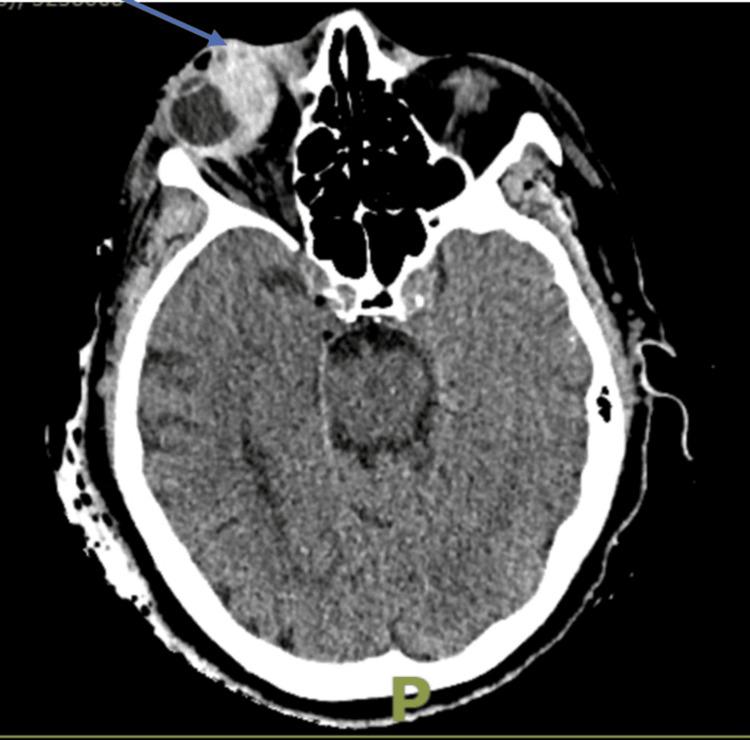

This report highlights a rare instance of spontaneous medial rectus haematoma in a 77-year-old female, attributed to warfarin use, underscoring its clinical significance. The patient initially presented with acute right eye pain, peri-orbital swelling, and reduced vision. Examination revealed a tense globe and elevated intraocular pressure (IOP), prompting emergency lateral canthotomy and inferior cantholysis. However, despite the initial procedure, her IOP remained elevated, indicating direct pressure from the haematoma on the globe and necessitating additional upper and lower eyelid lateral cantholysis. Medical management was also initiated to control the IOP. Over four months, the patient's visual acuity improved significantly, although a relative afferent pupillary defect persisted. This case underscores the rarity of spontaneous medial rectus haematoma in anticoagulated patients and highlights the critical importance of vigilant international normalized ratio (INR) monitoring and timely intervention to reduce morbidity and the risk of vision loss.